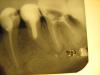

КТА Опубликовано 8 июля, 2011 Автор Поделиться Опубликовано 8 июля, 2011 Бред.Ультразвуком или бором "вытяните" устья к внешней дистальной стенке зуба и увидите истинные устья.пользуясь вашими рекомендациями прошла оба дистальных канала, промыла парканом, оставила кальций вот что получилосьснимок, правда не очень 1 Ссылка на комментарий

КТА Опубликовано 9 июля, 2011 Автор Поделиться Опубликовано 9 июля, 2011 Отлично! До какого размера расширили?до 35, при чем, прошла, не прикладывая больших усилий, как вы и говорили Видите какая вы молодец, взяли себя в руки и все получилось.благодоря вам, я была уверена в своих действиях Ссылка на комментарий